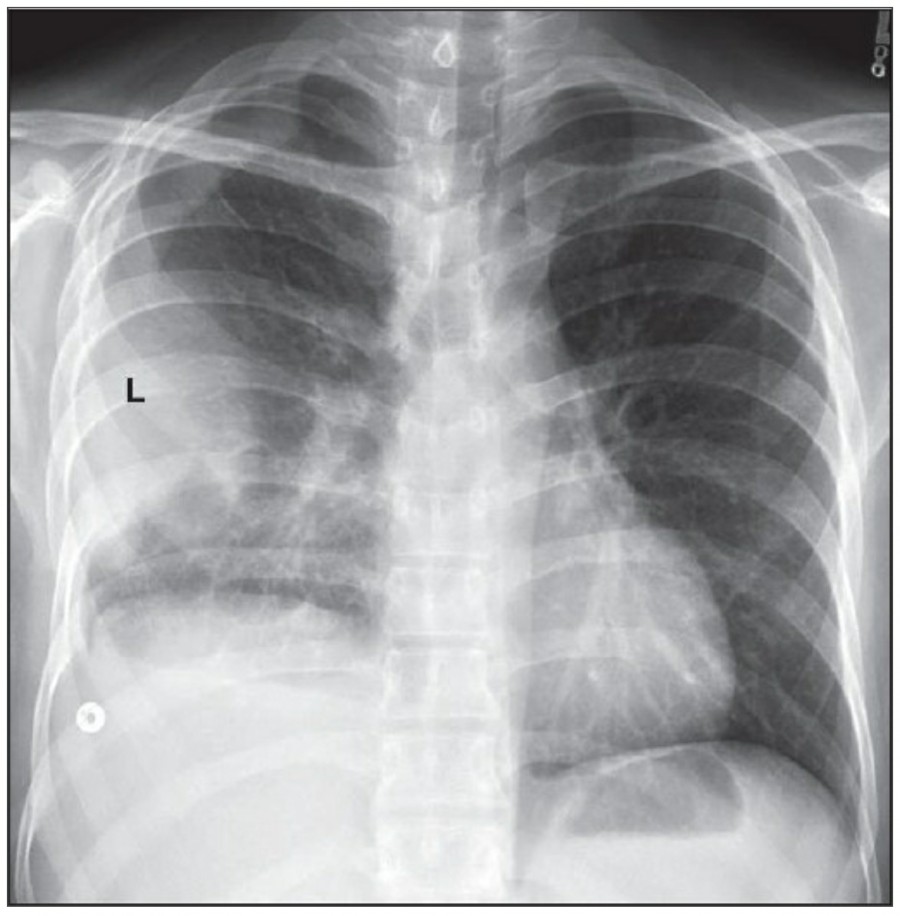

Pneumothorax

공기는 nondependent position으로 위치하므로, X ray상에서는 환자 자세에 따라 다르게 나타난다. Erect position에서 공기는 lung의 apicolateral surface에 위치하고 얇고 하얀 pleural line이 나타나며 그 뒤로 lung marking이 보이지 않는다.

하지만 pleural line 뒤로 lung marking이 존재한다고 해서 pneumothorax를 배제할 수 없다. Pneumothorax의 진단은 특히 parenchymal disease가 있을 때 진단하기 힘든데, 이는 compliance의 변화 때문에 collapse가 잘 안 되기 때문이다. Skin fold가 pneumothorax와 비슷하게 보이기도 한다.

중환자에서 pneumothorax의 진단은 종종 supine radiograph에서 내릴 수 있다. Supine position에서 공기는 anteromedial 방향으로 모이게 되는데, apical air collection이 있을 경우 large pneumothorax가 있음을 시사한다. 공기는 lung과 diaphragm 사이의 subpulmonic location에 trap 되어 있을 수도 있다. 공기가 costophrenic sulcus로 anterolateral extension 될 경우, 이 costophrenic sulcus의 radiolucency를 증가시키는데, 이를 deep sulcus sign이라고 한다. Subpulmonic pneumothorax의 다른 특징으로 diaphragm의 superior surface와 IVC 윗부분이 뚜렷하게 보일 수 있다.

중환자에서 tension pneumothorax의 진단은 매우 힘들다. ARDS와 같은 lung의 병리적인 기전이 lung compliance를 감소시킴으로써 total lumg collapse를 막는다. 또한 tension pneumothorax의 특징인 mediastinal shift가 PEEP으로 인해 나타나지 않을 수 있다. Chest X ray 상에서 tension pneumothorax는 hemidiaphragm의 depression이나 heart border, SVC, IVC의 이동으로 나타날 수 있다.